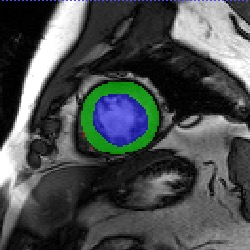

Transformers, the default model of choices in natural language processing, have drawn scant attention from the medical imaging community. Given the ability to exploit long-term dependencies, transformers are promising to help atypical convolutional neural networks (convnets) to overcome its inherent shortcomings of spatial inductive bias. However, most of recently proposed transformer-based segmentation approaches simply treated transformers as assisted modules to help encode global context into convolutional representations without investigating how to optimally combine self-attention (i.e., the core of transformers) with convolution. To address this issue, in this paper, we introduce nnFormer (i.e., Not-aNother transFormer), a powerful segmentation model with an interleaved architecture based on empirical combination of self-attention and convolution. In practice, nnFormer learns volumetric representations from 3D local volumes. Compared to the naive voxel-level self-attention implementation, such volume-based operations help to reduce the computational complexity by approximate 98% and 99.5% on Synapse and ACDC datasets, respectively. In comparison to prior-art network configurations, nnFormer achieves tremendous improvements over previous transformer-based methods on two commonly used datasets Synapse and ACDC. For instance, nnFormer outperforms Swin-UNet by over 7 percents on Synapse. Even when compared to nnUNet, currently the best performing fully-convolutional medical segmentation network, nnFormer still provides slightly better performance on Synapse and ACDC.